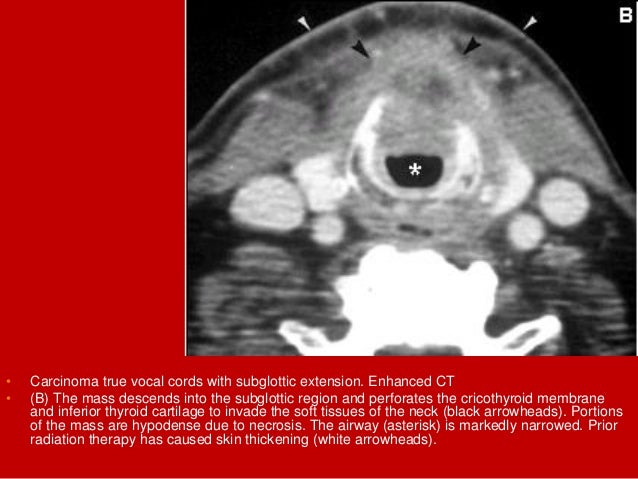

60. 60. • Carcinoma true vocal cords with subglottic extension. Enhanced CT (A) demonstrates thickening of the anterior commissure (arrow) by a mass involving both true vocal cords.

61. 61. • Carcinoma true vocal cords with subglottic extension. Enhanced CT • (B) The mass descends into the subglottic region and perforates the cricothyroid membrane and inferior thyroid cartilage to invade the soft tissues of the neck (black arrowheads). Portions of the mass are hypodense due to necrosis. The airway (asterisk) is markedly narrowed. Prior radiation therapy has caused skin thickening (white arrowheads).